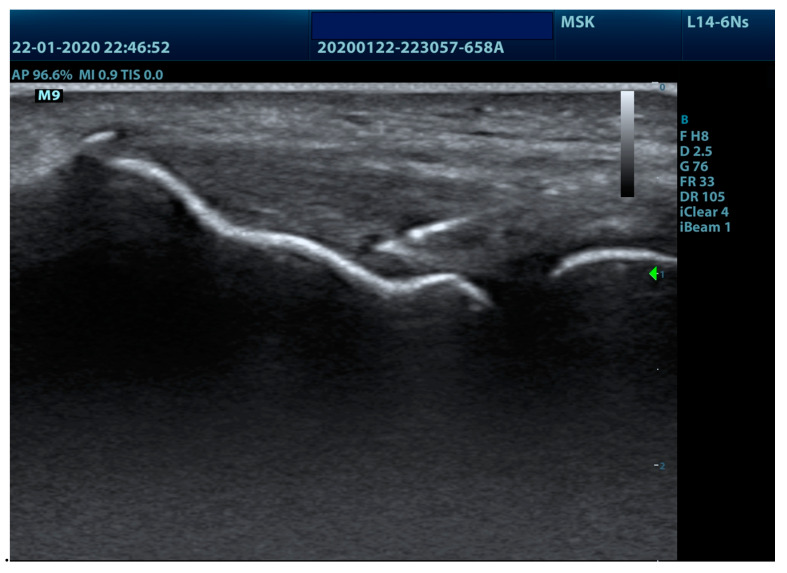

The application of the percutaneous electrolysis technique was performed with an EPTE® percutaneous electrolysis device (Ionclinics & A. Deionic SL, Valencia, Spain) for 1.2 min at an intensity of 350 µA in the insertional tendon of the muscles of the epicondyle (Figure 1) using a 0.3 mm needle guided by ultrasound (Voluson 730 pro, General Electric®, Boston, MA, USA) and forming an angle of between 30° and 45° with the axis thereof (Figure 2). The treatment was performed once a week for four weeks [6].

Figure 2.

Ultrasound imaging of lateral epicondyle needling.